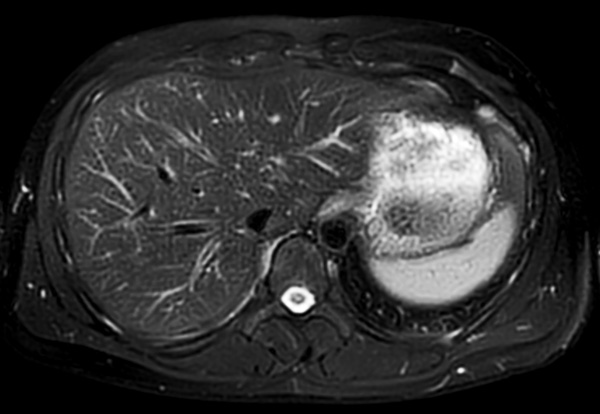

Axial T2w MultiVane XD (high res)